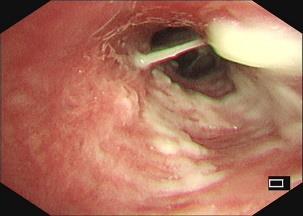

• 获得性免疫缺陷综合征合并马尔尼菲篮状菌导致肠道感染的内镜下表现(附6例报告)

2026, 32(3):84-88. DOI: 10.12235/E20250461

摘要 (32) HTML (27) PDF 3.50 M (26) 评论 (0) 收藏

摘要:目的 探讨获得性免疫缺陷综合征(AIDS)合并马尔尼菲篮状菌(TM)感染导致肠道感染的内镜下特征。方法 回顾性分析2022年11月-2024年10月于该院确诊为AIDS合并TM感染导致肠道感染的6例患者的临床资料。包括:临床症状、实验室检查、影像学检查、内镜检查和病理检查等。结果 6例患者中,男5例,女1例;发病年龄26~67岁;AIDS合并TM感染导致肠道感染患者的临床表现为:腹泻、腹痛、腹胀和恶心呕吐。其中,2例有消化道出血表现。实验室检查:6例患者外周血白细胞计数为(1.37~4.49)×109/L,血红蛋白计数为(67~99)g/L;CD4+T淋巴细胞为(1~52)个/μL,CD8+ T淋巴细胞为(61~321)个/μL,CD4+T淋巴细胞/CD8+T淋巴细胞比值为(0.01~0.18)。6例患者均行HIV RNA检测。其中,5例HIV RNA阳性。血培养:可见丝状真菌,报告显示为TM。影像学检查:6例患者CT结果可见肠系膜及腹膜后多发淋巴结肿大。内镜检查:6例患者内镜下均可见肠道病变。其中,十二指肠糜烂溃疡2例,结肠多发糜烂溃疡4例。病理检查:6例患者幽门螺杆菌(Hp)结果均为阴性,黏膜下可见成簇的小球形真菌孢子,符合TM感染;特殊染色:PAS(+),六胺银染色(+)。结论 当AIDS晚期患者出现消化道症状时,应警惕TM感染,病变部位常见于全结肠和直肠,亦可累及十二指肠,内镜下表现多为溃疡、糜烂和隆起性病变,形态表现无特异性;及时行胃肠镜检查、病理活检、特殊染色和免疫组化是确诊的关键。